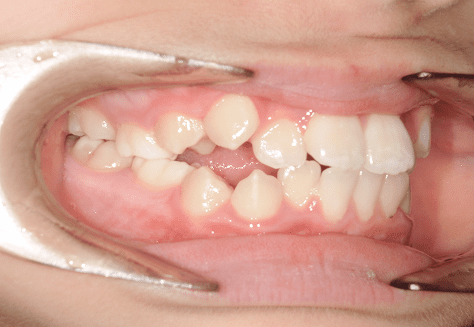

M.H

治療前

治療後

主訴

前歯が出ている。下の歯並びが特に気になる。奥歯でしっかり噛めない。

診断

上顎前突・叢生・シザーズバイト

年齢/性別

20代/男性

抜歯部位

下顎両側大三大臼歯(口腔外科にて)

上顎両側第一小臼歯・下顎左側側切歯

(当院にて5,500円×3) -

使用装置

上下エッジワイズ→インビザライン(PBM使用)

保定装置

上下ビベラリテーナー

料金

初回資料採得・・・・・・・30,000円

診断料・・・・・・・・・・33,000円

動的治療終了時資料採得・・5,500円 -

基本料金

880,000円

診察料金

5,500円×44回

-

治療期間

3年6カ月